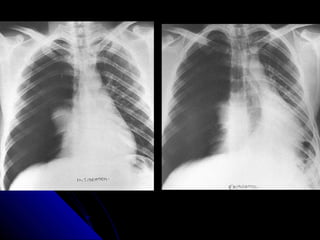

IInnssppiirraattiioonn EExxppiirraattiioonn

TThhee lleevveell ooff iinnssppiirraattiioonn ccaann bbee eessttiimmaatteedd

bbyy ccoouunnttiinngg rriibbss.. VViissuuaalliizzaattiioonn ooff nniinnee

ppoosstteerriioorr rriibbss,, oorr sseevveenn aanntteerriioorr rriibbss oonn aann

uupprriigghhtt PPAA rraaddiiooggrraapphh pprroojjeeccttiinngg aabboovvee

tthhee ddiiaapphhrraaggmm wwoouulldd iinnddiiccaattee aa

ssaattiissffaaccttoorryy iinnssppiirraattiioonn..